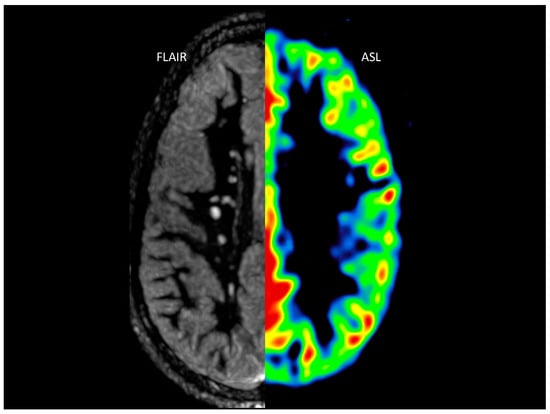

2.2. Cerebral Magnetic Resonance

Postprocessing